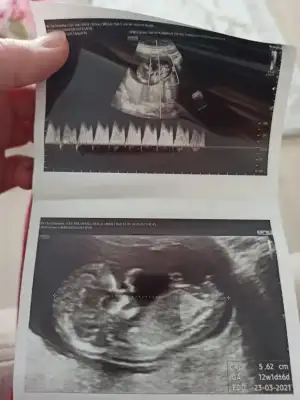

dr soylemeden siz gorun genital nub teorisi ( bebegin cinsiyeti)

SevgiliMerhabalar tecrübeli arkadaşlar lütfen benimkini de söylemisiniz sizce cinsiyeti nedir ? 10+5 günlük ultrason

Bu USG kaç haftalık 11 12 13 haftalar olmalı sanki kız gibi geldiIkra meyra biz cinsiyetimizi öğrendik sence

Hiç net değil 12 13 haftalar olunca tekrar USG paylasin sanki kız ama emin olamadimMerhabalar tecrübeli arkadaşlar lütfen benimkini de söylemisiniz sizce cinsiyeti nedir ? 10+5 günlük ultrason

Ikra meyra 12+2 yiz bugün kendi hastanemde çalıştığım perinatoloji bölümünde ikili tarama testi için muayene oldum doktor hanım cinsiyet için bişey diyemem daha çok küçük dedi medipolde ki doktorum da erkeğe benziyor demişti sizde erkek dediniz tekrar resim atayım dedim

Evet hala erkek diyorumIkra meyra 12+2 yiz bugün kendi hastanemde çalıştığım perinatoloji bölümünde ikili tarama testi için muayene oldum doktor hanım cinsiyet için bişey diyemem daha çok küçük dedi medipolde ki doktorum da erkeğe benziyor demişti sizde erkek dediniz tekrar resim atayım dedim

Kız gibi sanki emin olamadım tekrar USG paylasirmisin 11 12 13 haftalar olmalıMerhaba benim de 12+4 tahmin yapabilirseniz sevinirim.